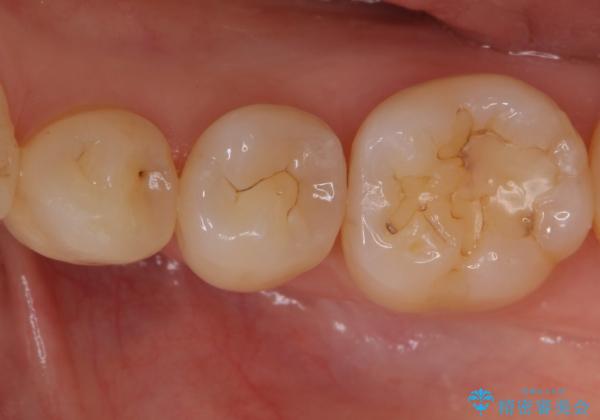

変色しない材料での治療をご希望されたためセラミックインレーでの治療をしていくこととなりました。

- 左下6 セラミックインレー 77,000円×1本費用は治療当時の料金となります

継ぎ接ぎになった樹脂の詰め物から一塊のセラミックインレーに置き換えることで着色や二次う蝕のリスクを抑えます。